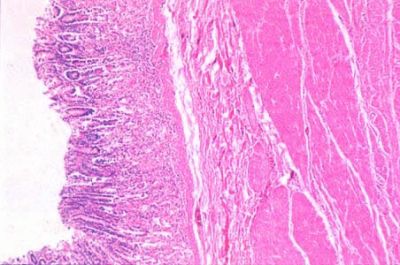

Pyloric region of stomach - histology slide

This is a histology slide from the pyloric region of the stomach. This differs from the fundic portion in that the gastric pits are deeper and there are pyloric glands in the lamina propria.